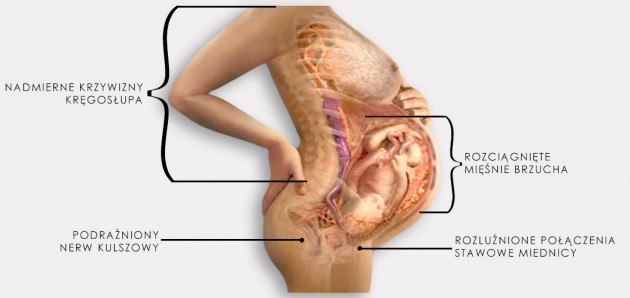

Rozejście spojenia łonowego jest zaś skutkiem nadmiernego rozluźnienia więzadeł i zwiększenia ruchliwości kości miednicy pod wpływem hormonów ciążowych (estrogenów). Hormony te wpływają zarówno na chrząstkozrost łonowy jak i stawy krzyżowo-biodrowe. Pojawia się ból w trakcie chodzenia („kaczy chód”), a niekiedy słyszy się nawet w trakcie chodzenia charakterystyczne trzaski. Niemożliwe staje się stanięcie na jednej nodze. Do rozejścia się spojenia łonowego (jak również jego pęknięcia a nawet rozerwania) może dojść w trakcie trudnego porodu, gdy istnieje niewspółmierność porodowa lub konieczne było użycie kleszczy.

POSTAWA KOBIETY CIĘŻARNEJ